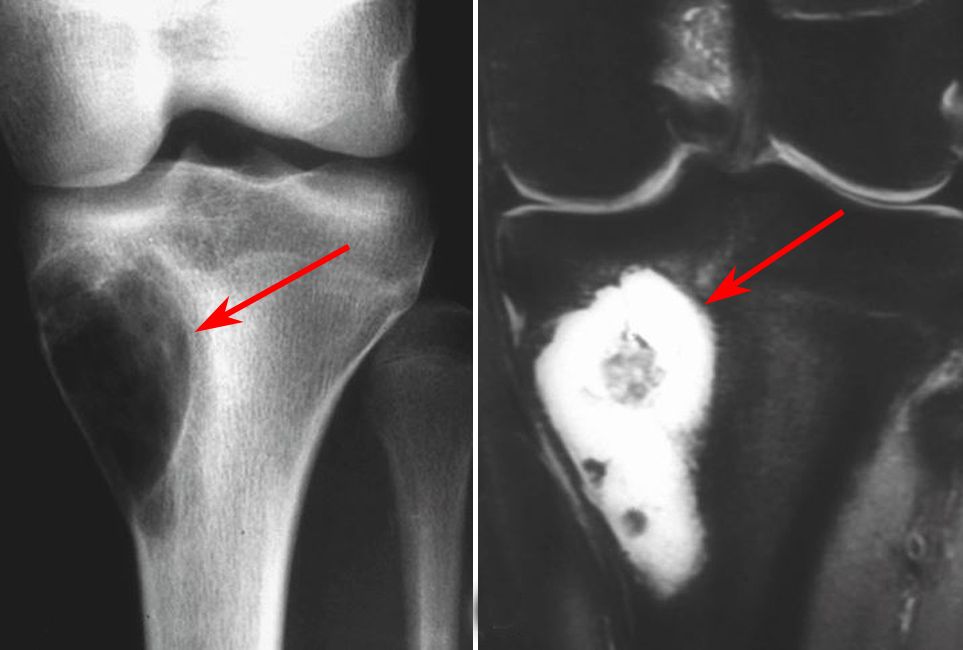

Image